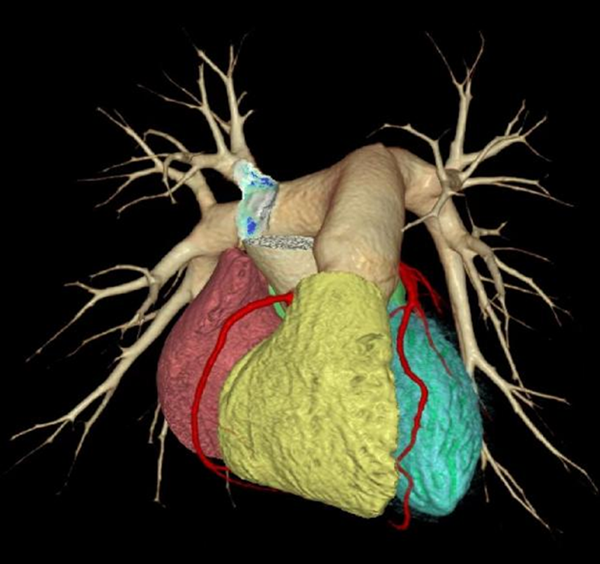

该320排640层螺旋CT机架,旋转速度为0.25s/圈,探测器单圈覆盖可达到16cm。在心血管检查方面,其AI冠脉追焦技术,可在任意心率和心律条件下实现单心动周期内成像,即在一次心跳的瞬间便可获取从心底到心尖完整的全心范围扫描数据,无需进行呼吸训练和吸气憋气,让严重心律不齐、房颤、房扑或超高心率等患者在冠状动脉成像上几乎不受限制,极大提升了心血管患者的检查效率。